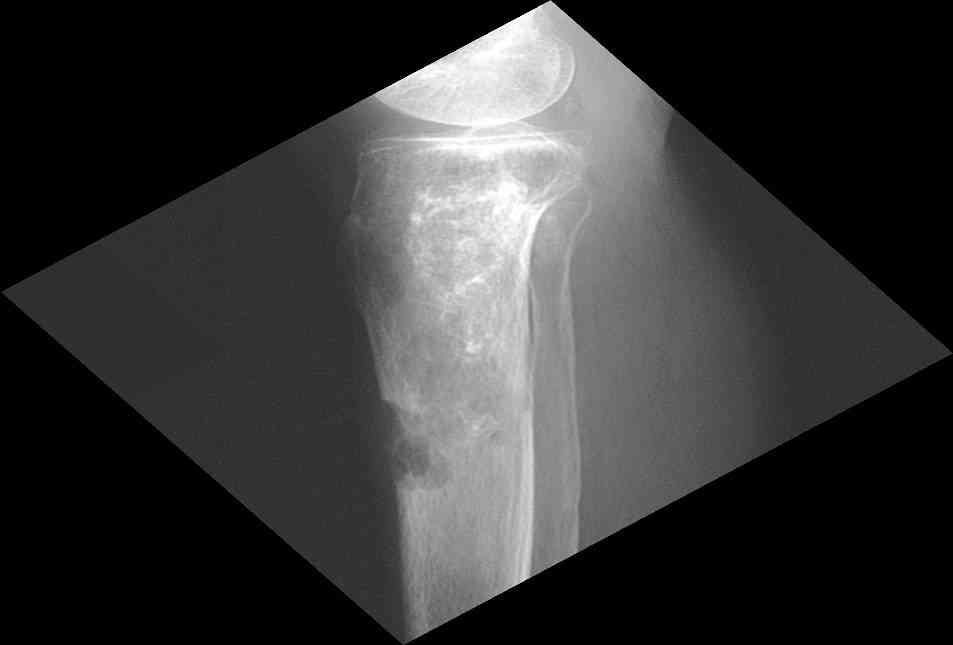

Изменения структуры костей у Вашего пациента больше похожи на полиоссальную форму фиброзной дисплазии или болезнь Педжета, возможены также инфаркты костного мозга б.берцовых костей. К сожалению, качество снимка не очень хорошее, непонятно, сохранен ли кортикальный слой б.берцовых костей по передней поверхности.

Для примера привожу случай из архива американской ассоциации рентгенологов (ACR) - развитие злокачественной фиброзной гистиоцитомы на левой б.берцовой кости у пациента с множественными инфарктами костного мозга (рис 4,5 - левая, рис 6 - правая)